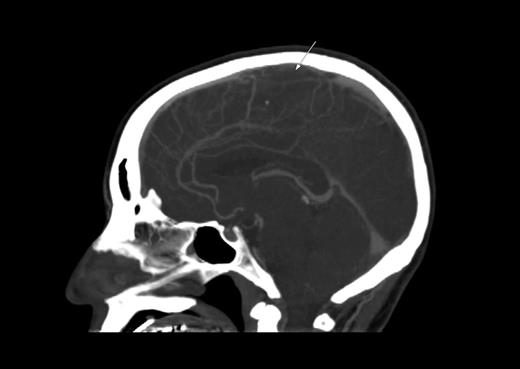

L-Asparaginase–associated thrombosis

A 35-year-old man with B-lineage ALL is treated with a standard ALL protocol.55 On day 17 of induction, Escherichia coli L-asparaginase (L-ASP) is started at a dose of 10 000 units/day in combination with prophylactic subcutaneous low molecular weight heparin (LMWH). Pretreatment thrombin time, partial thromboplastin time, fibrinogen, and D-dimer levels are normal. On day 9 of L-ASP, he presents with generalized seizure, right-sided limb weakness, and slurred speech. CT scan discloses extensive sagittal sinus thrombosis (Figure 2). L-ASP treatment is discontinued and full dose heparin is initiated. There is no evidence of inherited thrombophilia.

CT scan. Sagittal plane demonstrating sagittal sinus. The arrow indicates the filling defect corresponding to sagittal sinus thrombosis.

We treat CNS thrombosis with full-dose heparin coupled with intensive cryoprecipitate and platelet transfusion support. Sagittal sinus thrombosis is often accompanied by increased intracranial pressure and secondary hemorrhagic infarct. We continue heparin, even in the presence of such hemorrhage with blood product support and frequent CT/MRI monitoring, because the primary event is thrombosis. Importantly, for the same reason, L-ASP may be resumed at lower doses if toxicity was not greater than grade 3 and completely resolved.59,65